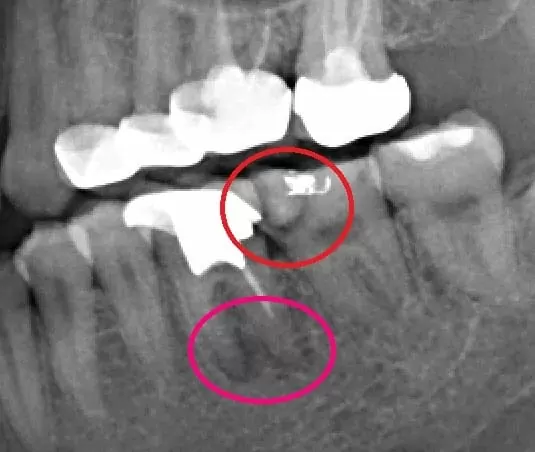

1.抽痛的主要來源並非已根管治療過後的左下第一大臼齒,而是左下第二大臼齒二次齲齒導致,且齲齒範圍已經靠近牙髓腔,因此導致患者自發性抽痛。(如上圖中紅色圈)

2.導致悶脹不舒服的主因則是已根管治療過後的左下第一大臼齒,之前的根管治療並未達到裡想的工作長度與寬度,殘留的牙髓神經組織並未清潔乾淨,導致根管慢性發炎且嚴重鈣化,細菌往下侵蝕並蔓延至齒槽骨,造成患者咬痛或悶脹感。(如上圖中粉色圈)